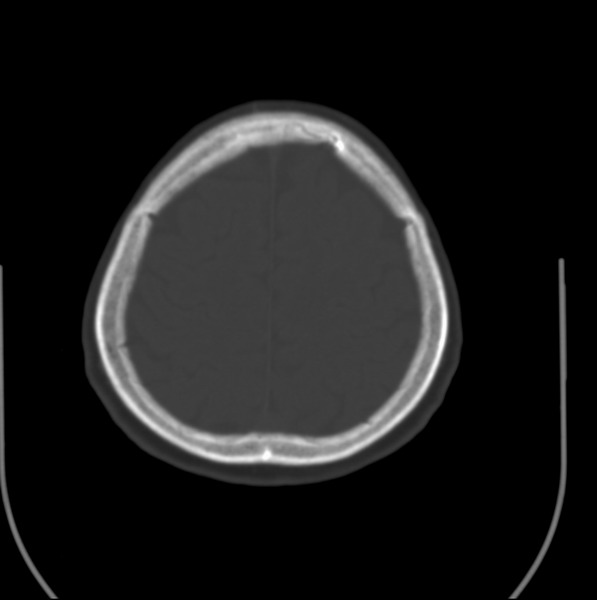

以下是引用余辉在2009-4-25 10:34:00的发言:[br]上矢状窦旁软组织肿块,内有钙化,与上矢状窦边界不清,灶后颅骨内板骨质增生硬化,支持考虑脑膜瘤,建议增强

以下是引用hmyj9在2009-4-25 14:21:00的发言:[br]病灶紧贴颅板处,中心高密度周围见软组织密度,局部颅板有增生,支持脑膜瘤诊断,建议增强。

以下是引用边生丽在2009-4-25 11:55:00的发言:[br][br] [br] 考虑脑膜瘤可能性大;建议行进一步检查。 [br] [br] [br]